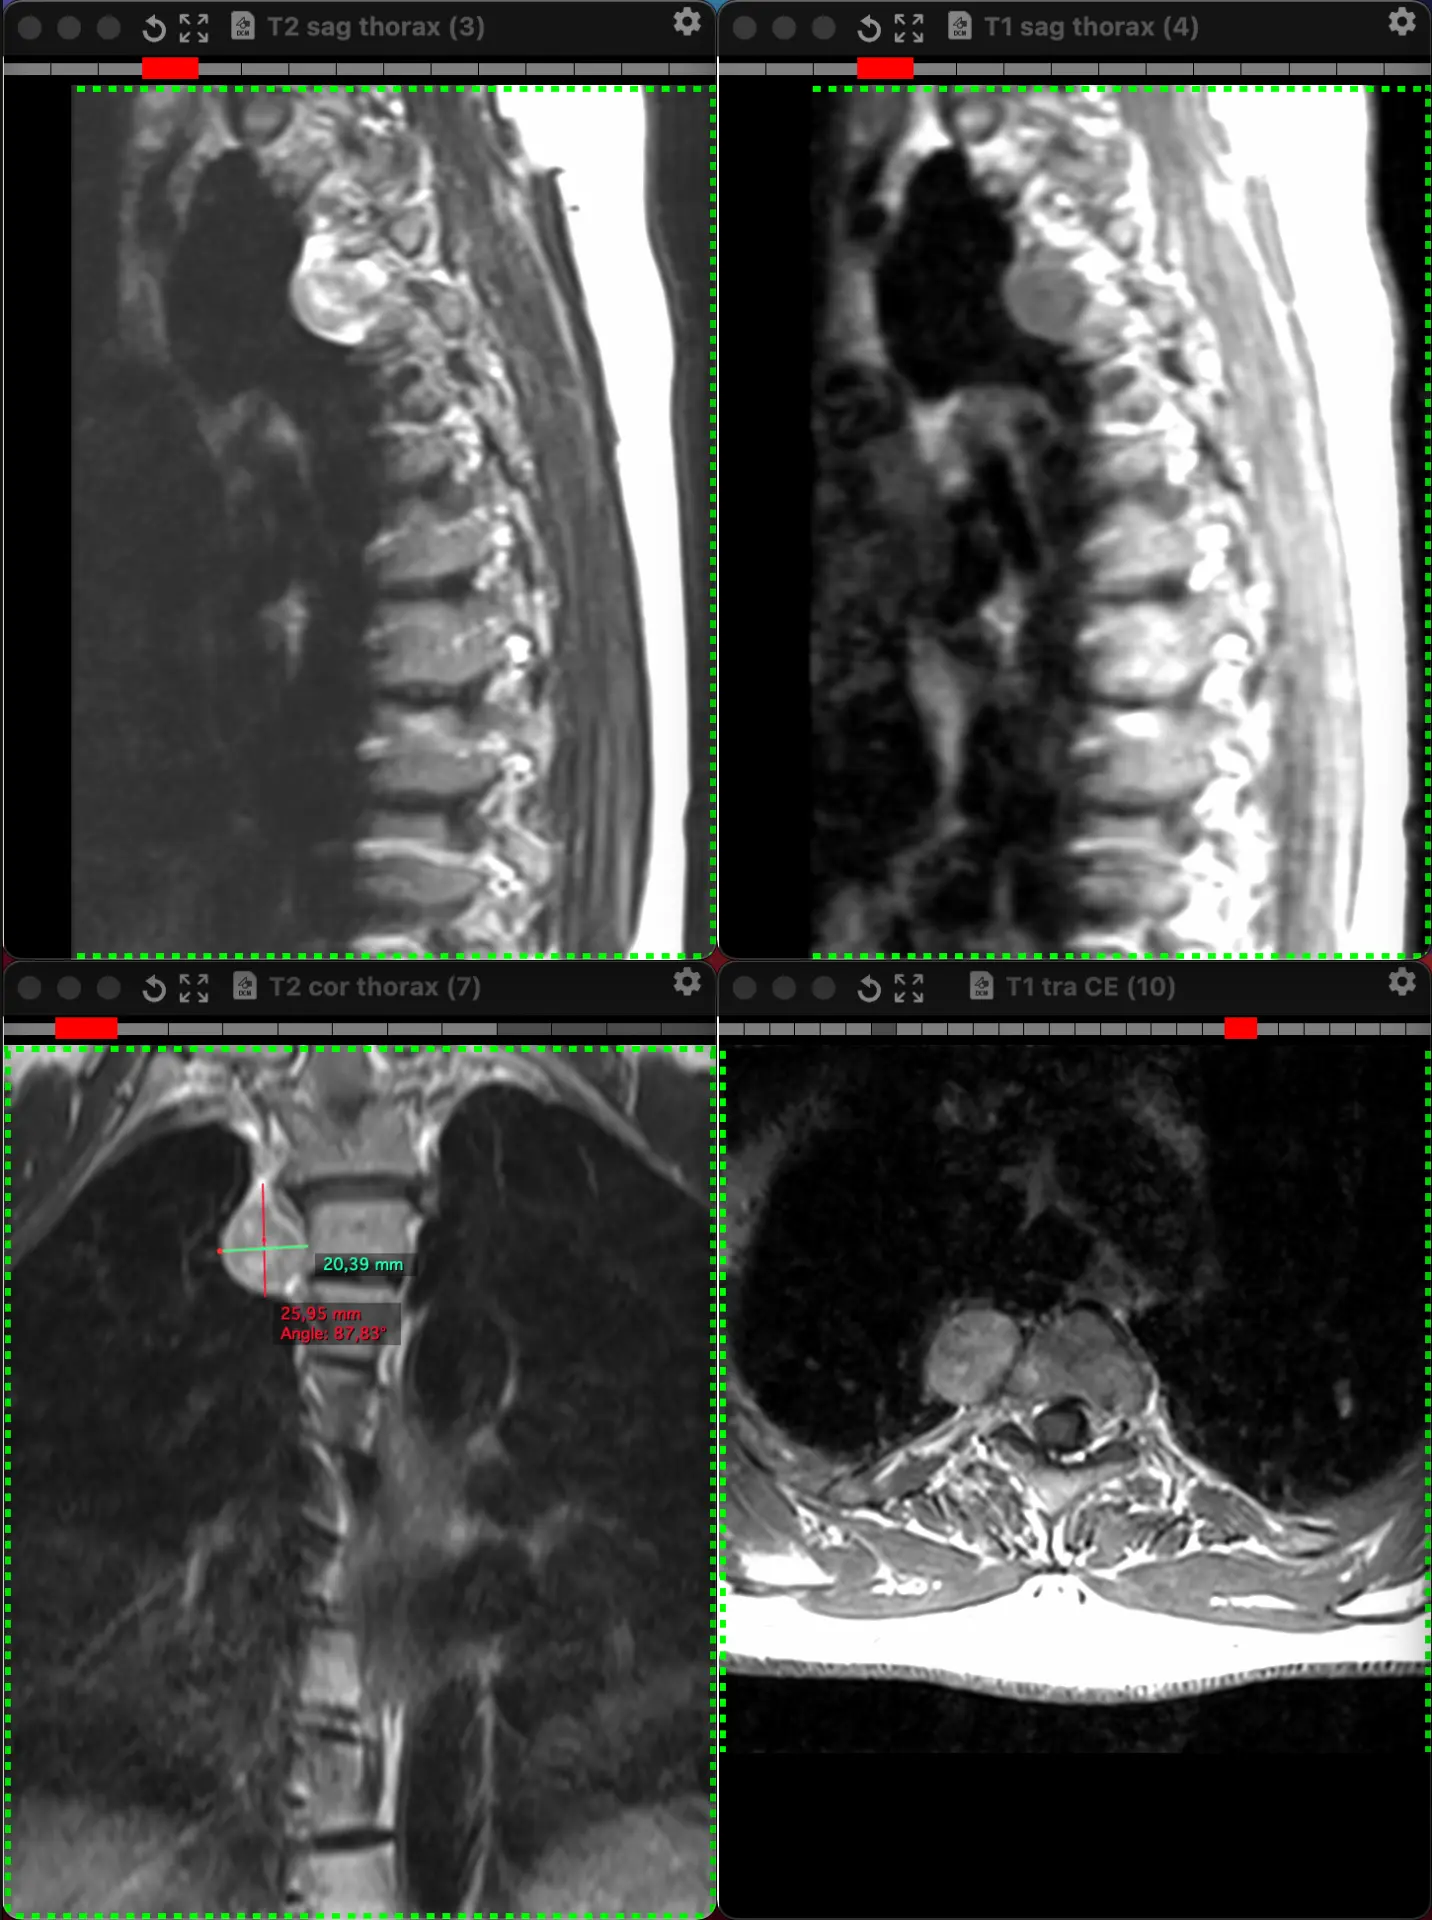

И ещё одна предполагаемая шваннома заднего средостения у женщины, на сей раз 38 лет, обследованной не по её поводу. Бессимптомная, как и почти всегда.

👍 45

Небезосновательно предполагаемая шваннома заднего средостение у женщины 54 лет, обследованной не по её поводу. Бессимптомная, как и почти всегда.

Опухоли нервной системы чаще всего встречаются среди первичных новообразований средостения. Львиная доля их — доброкачественные. Шванномы — самые частые нейрогенный опухоли в грудной клетке, которые развиваются из шванновских клеток периферических нервов (причём, любых, вплоть до самых мелких и необязательно спинномозговых) и часто сидят в заднем средостении. Обнаруживаются почти всегда случайно при проведении различных методов визуализации.

Интраторакальная шваннома чаще всего расположена в заднем средостении. Это - медленно растущая доброкачественная опухоль с низкой вероятностью стать злокачественной. В крайне редких случаях злокачественной трансформации могут встречаться плеоморфные веретенообразные клетки и некротические и геморрагические изменения. Как и в данном случае, опухоль обнаруживается случайно при визуализации: эхокардиография, гастроэндоскопия, КТ или МРТ. Симптомы в подавляющем большинстве случаев, отсутствуют, но могут появиться, если опухоль начнет давить на окружающие органы.